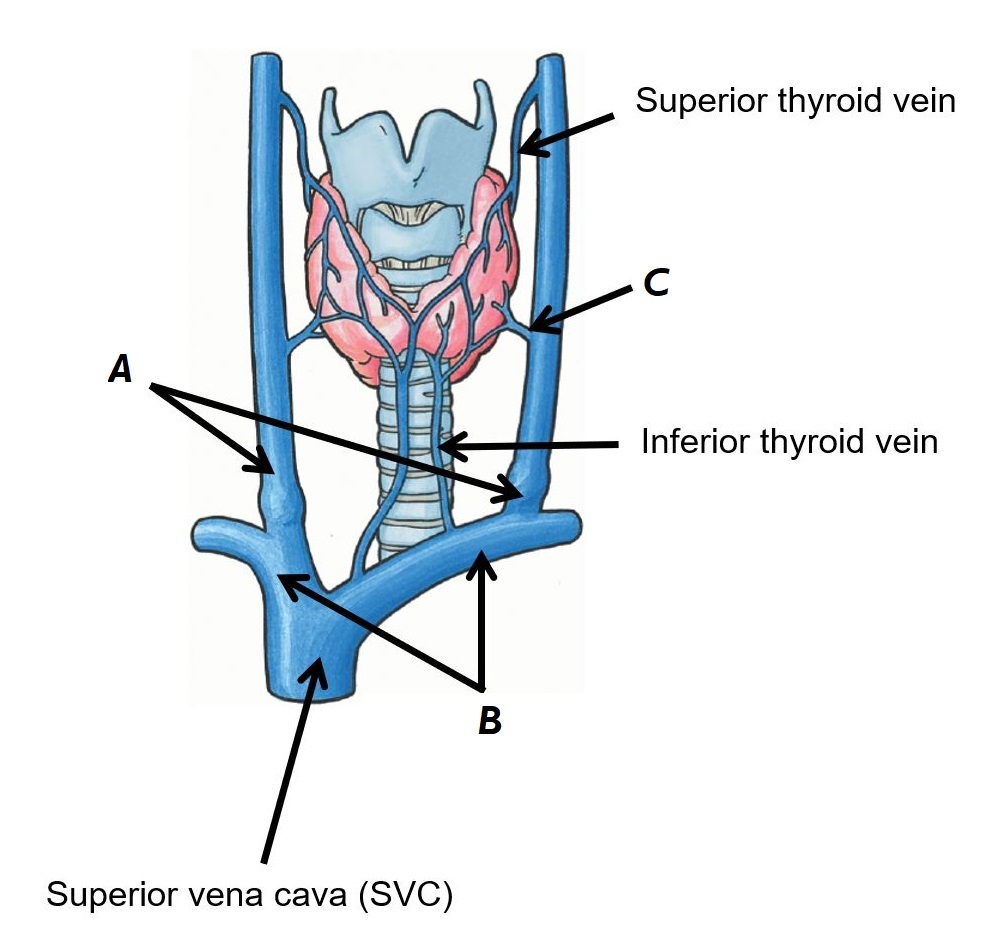

Name vessels A, B and C

A - Internal jugular veins

B - Brachiocephalic veins

C - Middle thyroid vein